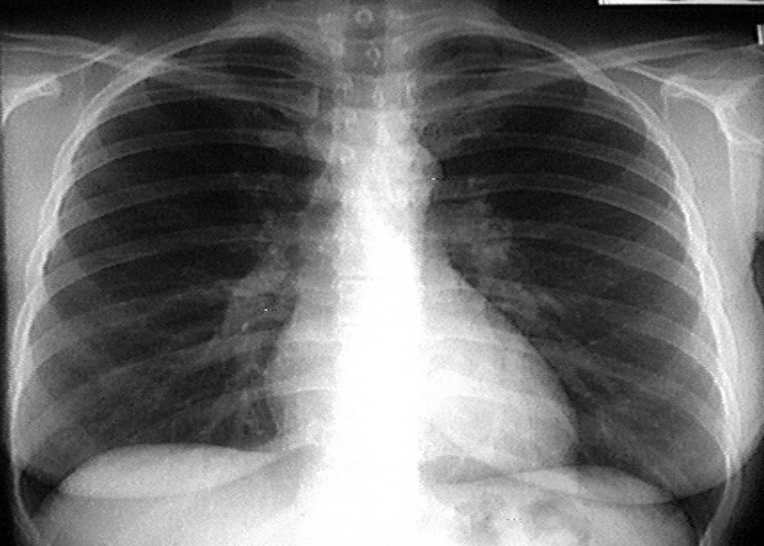

AP chest X-ray (critically ill patient and intubated)

tracheal intubation (above the carnia. if lower it will inter right main stem bronchous→leads ti left lung collaps)

NG tube

Central line (into SVC)

left main stem bronchous showing radio-opacity and patent bronchioles→Air broncho-grams (if localised→indicates infectious process)

Bilateral diffuse lung opacities on both lung fields (slightly more on left side)

Ddx: ARDs, decomensated heart failure, aspiration

Air bronchograms

AP chest X-ray